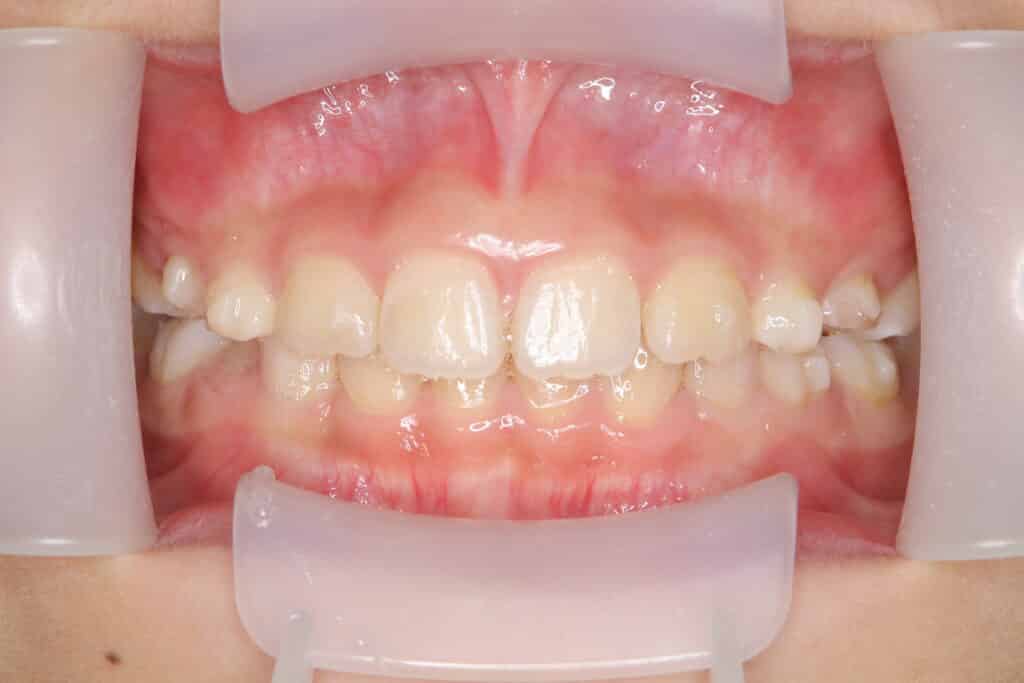

症例写真:現在【現在】(1年9か月経過)

マウスピースを1日18時間装着していただき、お口周りの筋肉を上手く使えるように、お口の筋肉トレーニングも同時に進めて、舌の位置が改善されました。

ご本人の努力もあって、上下の顎骨を大きくすることができ、初診時と比べて歯がきれいに並び、噛み合わせも良好に改善しました。

歯磨きの指導もさせていただき、毎日のブラッシングも丁寧にできるようになり、食後の習慣となったので口腔内環境が良く、治療がスムーズに進みました。